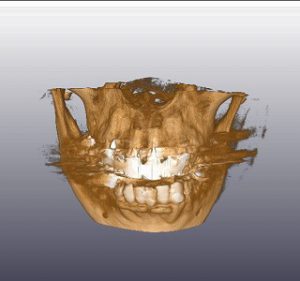

口腔外科(インプラント)、歯科・矯正歯科(歯列矯正)、 アメリカ式の根管治療(Endodontics,Rootcanal treatment),を中心に

虫歯治療、歯周病治療(歯槽膿漏)を総合的に治療し、お口の健康と若さを維持する治療を行っております。